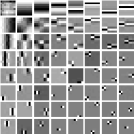

We pre-learn MARS models with different numbers of layers (depths) with transforms. The models are learned from overlapping patches extracted from five XCAT phantom slices. The number of pixels and the number of overall training patches are about and , respectively. The training slices are displayed in the supplement (Fig. 13). The patch stride is . We choose , , , , and layers, respectively, during training, which corresponds to ST, MARS2, MARS3, MARS5, and MARS7 models. We initialize the MARS learning algorithm with the 2D DCT matrix for the transform in the first layer and identity matrices for transforms in deeper layers. For each model, we ran 1000 to 1500 iterations of the block coordinate descent training algorithm to ensure convergence. We choose for ST, , , for MARS2, , , , , for MARS3, , , , , , , , , for MARS5, , , , , , , , , , , , , for MARS7. Fig. 3 shows some of the learned transforms, with each transform matrix row displayed as a square patch for simplicity. The first layer transform in the models typically displays edge-like and gradient filters that sparsify the image. However, with more layers, finer level features are learned to sparsify transform-domain residuals in deeper layers. Nonetheless, the transforms in quite deep layers could potentially be more easily contaminated with noise in the training data, since the main image features are successively filtered out over layers.